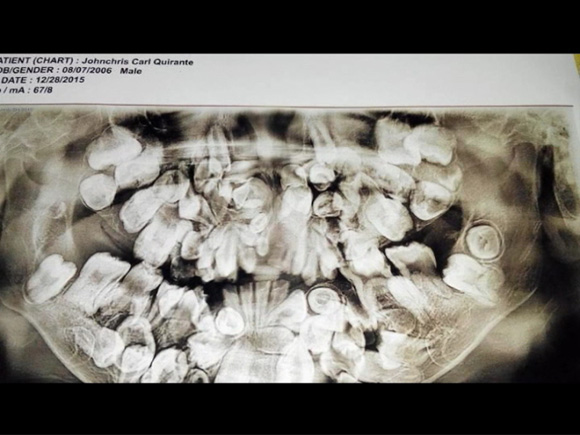

فلپائن کے 9 سالہ بچے کے 300 دانت

فلپائن میں 9 سال ایک بچے کے 300 دانت اسے بری طرح ستارہے تھے جنہیں ایک طویل آپریشن کے بعد نکال کر اسے معمولاتِ زندگی کے قابل بنایا گیا ہے۔

جان کرس نامی فلپائنی بچہ ''ہاپر ڈونٹیا'' کے مرض میں مبتلا ہے جس سے اس کے منہ کی حاشیوں کے علاوہ اس کے تالو اور دیگر جگہوں پر دانت تھے جن سے وہ بہت پریشان تھا یعنی اس کا منہ دانتوں سے بھرا ہوا تھا۔ جب وہ 2 سال کا تھا کہ اس وقت اس کے منہ میں 20 دانت ہونے چاہیے تھے لیکن اس وقت بھی وہ 50 دانت رکھتا تھا۔

5 سال کی عمر میں اس کے ایکسرے میں 150 دانت دکھائی دئیے جو اگلے 4 سال میں بڑھتے بڑھتے 300 کے قریب جا پہنچے اور یوں وہ ہر روز مشکلات کا شکار ہوتا گیا۔ بچے کو اس مشکل سے نجات دلانے کےلےی پہلے آپریشن سے اس کے 40 دانت نکال کر الگ کیے گئے جب کہ تمام اضافی دانتوں کو نکالنے کے لیے مزید 7 آپریشن کرنا ہوں گے۔